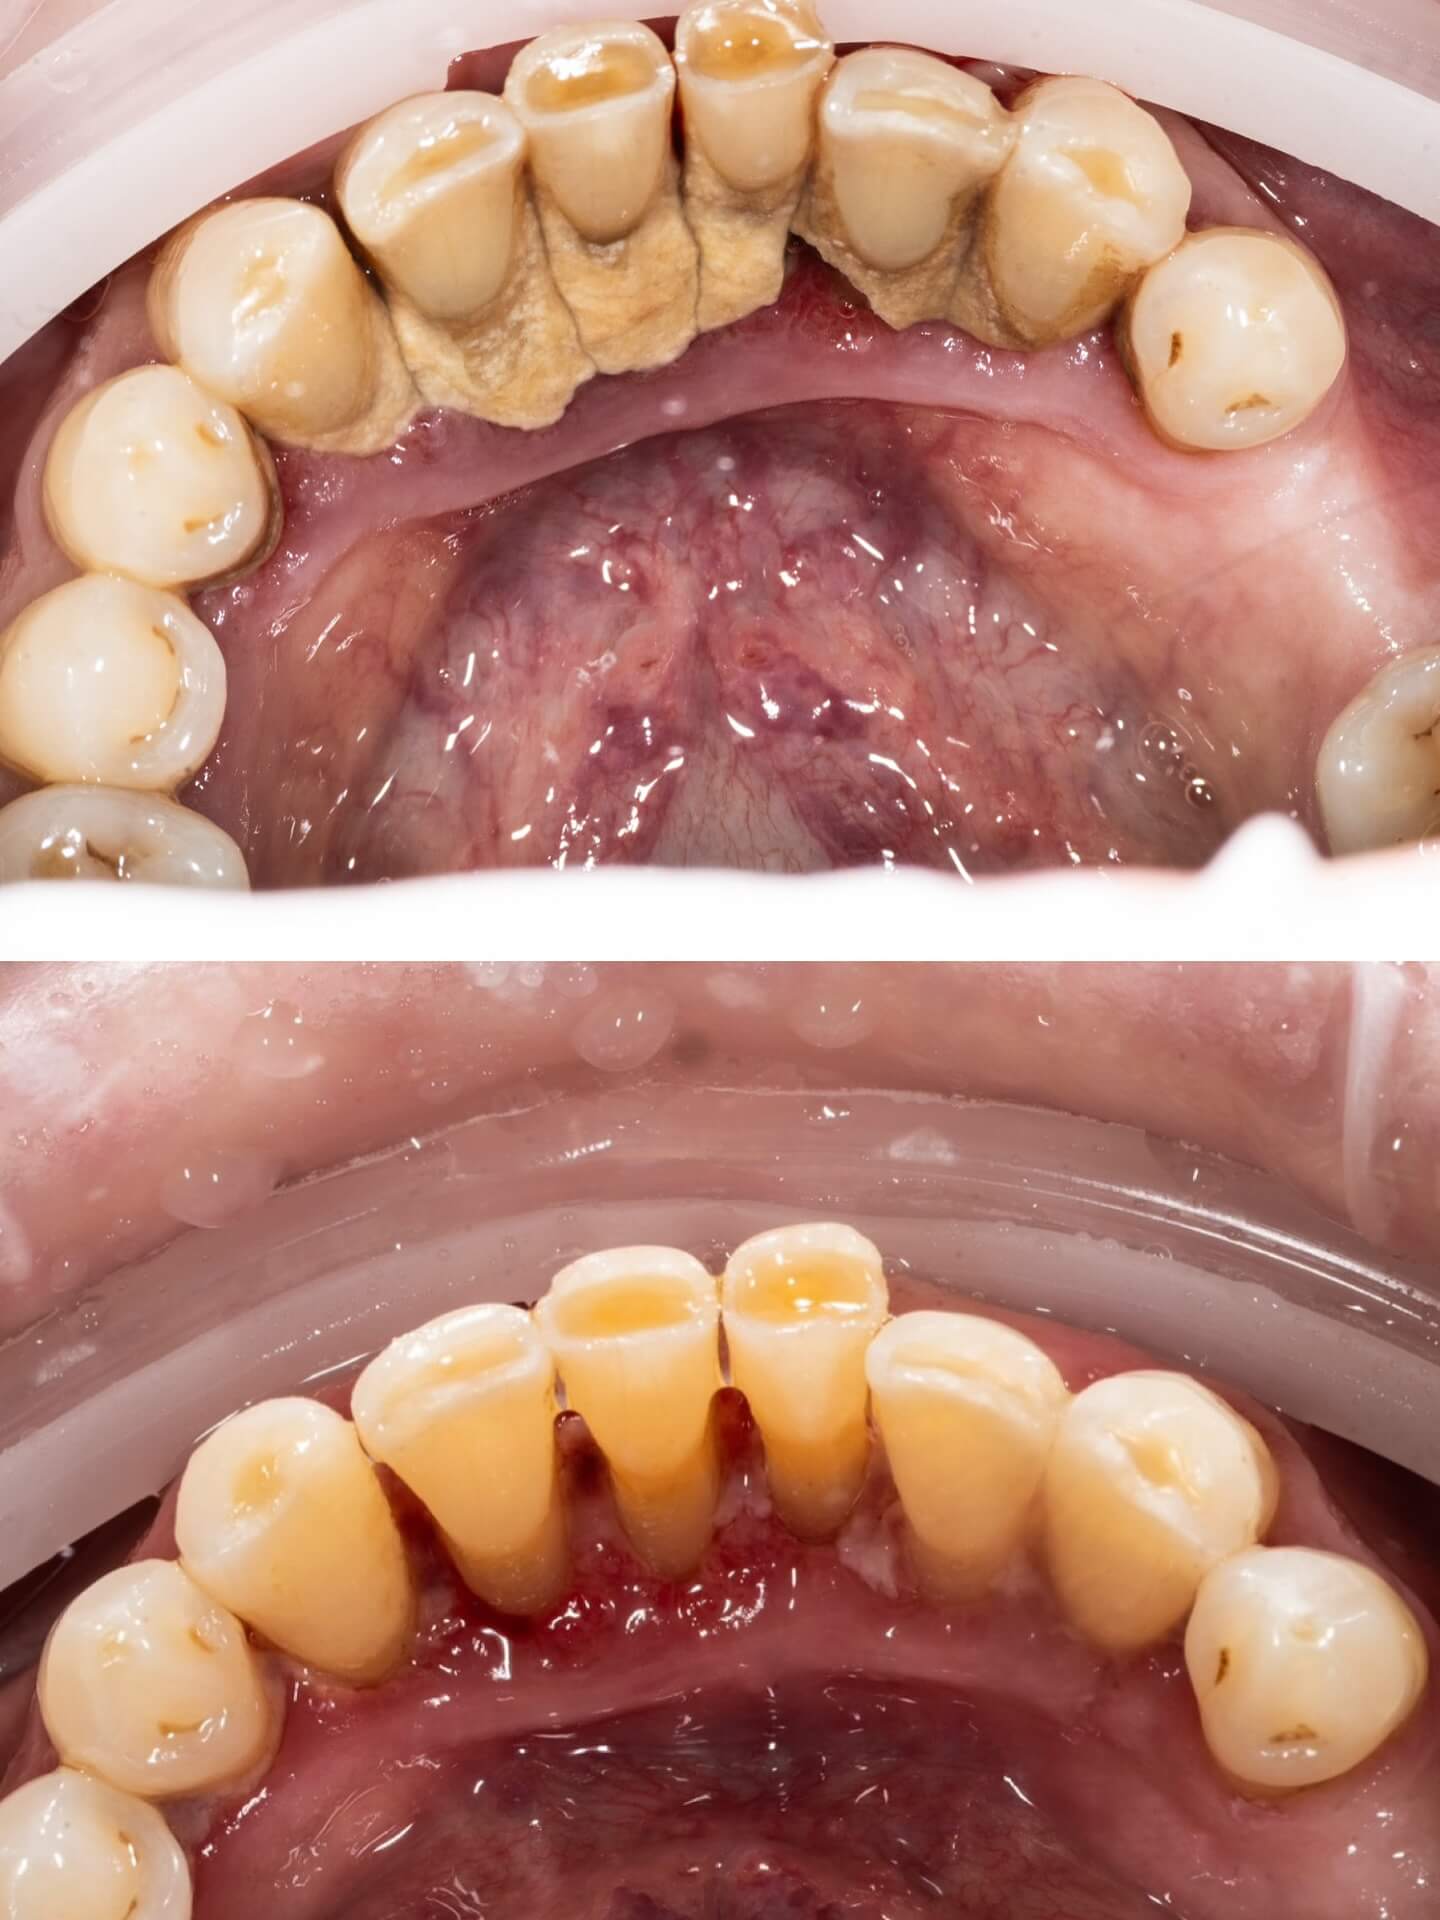

Înainte și după tratament

Dr. Ungureanu Dr. Ungureanu